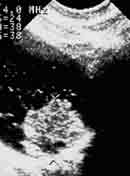

Эндовезикальное сканирование позволяет дифференцировать все слои мочевого пузыря (Рис. 1). Между мышечной стенкой и слизистой оболочкой визуализируется гипоэхогенная подслизистая соединительная ткань. При стадии рака мочевого пузыря Та (инвазия в пределах слизистой) создается впечатление, что опухоль отделена от мышечной стенки мочевого пузыря, то есть подслизистый слой остается неизмененным (Рис. 2), также хорошо визуализируются устья мочеточников. При распространении инвазии субэпителиальной соединительной ткани (стадия Т1) опухоль уже непосредственно прилежит к мышечному слою, но не инвазирует последний (Рис. 3).

Рис. 1. Цистэндосонограмма. Нормальная стенка мочевого пузыря.

1 - слизистая оболочка,

2 - подслизистая соединительная ткань,

3 - мышечная стенка.